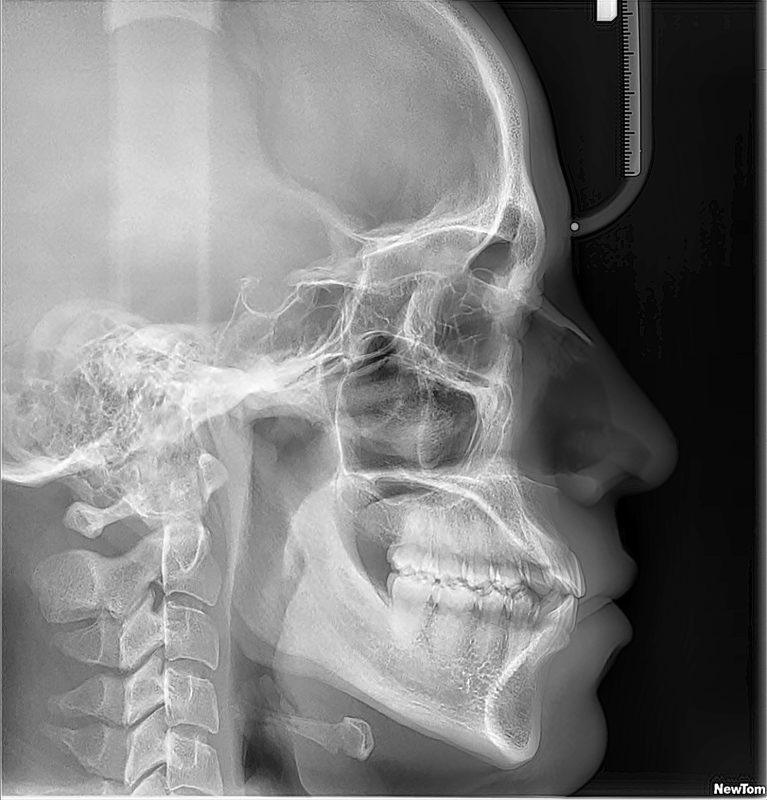

La radiografía de senos paranasales es una técnica de imagen que se utiliza para examinar las cavidades llenas de aire en los huesos que rodean la nariz, conocidas como senos paranasales. Incluyen los senos maxilares, etmoidales, esfenoidales y frontales. Puede ser realizada para diversos propósitos, como:

- Diagnóstico de sinusitis

- Evaluación de la anatomía

- Detección de tumores o quistes

- Evaluación de fracturas